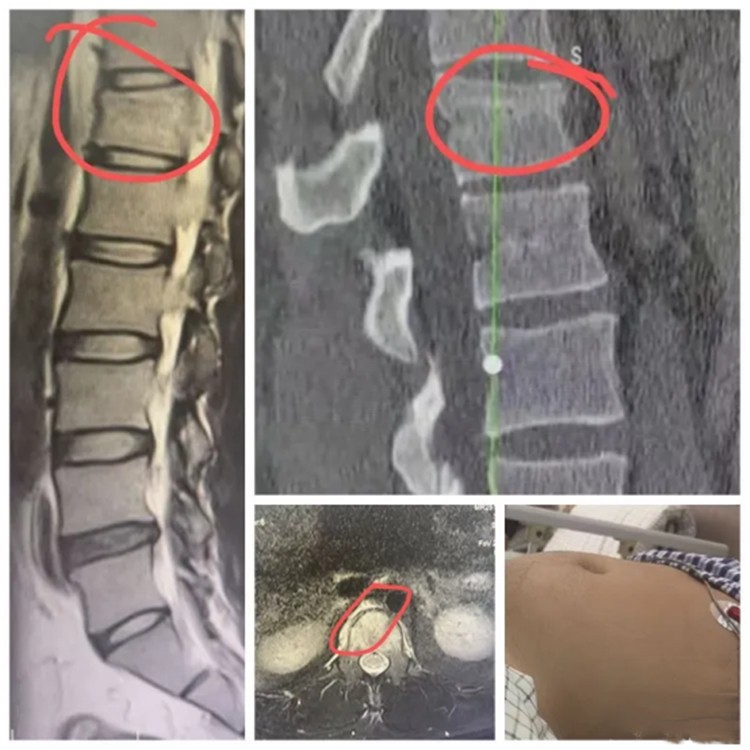

红网时刻新闻10月22日讯(通讯员 小姿)近日,一辆120急救车将一名因从卡车跌落受重伤的年轻男子紧急送至长沙泰和医院急诊科。患者入院后,经检查确诊为脊柱椎体前中柱压缩爆裂骨折,伴有椎体出血和腹膜后血肿。由于血肿压迫腹丛神经,还引发了麻痹性肠梗阻,导致腹部严重胀气,情况危急。

术前影像资料

考虑到传统开放手术创伤大、恢复慢,脊柱团队决定采用组合微创手术方案,以减小创伤、加快康复。从患者入院到进入手术室,仅用了约一小时。手术由多学科团队协作完成,全程微创操作,包括植钉、复位、减压、固定和植骨等关键步骤。手术历时两小时,出血量不足10毫升。